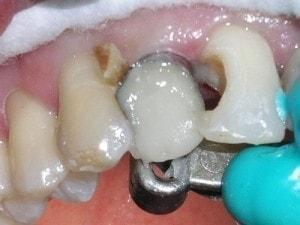

Apple core prep isolated with the Greater Curve Standard band

Matrix secured with Mega Bite (Discus Dental).

A portion of the matrix has been cut away intra-orally with a diamond or carbide to provide access. The distal contact opening will be established by smoothing away the matrix with a football finishing bur. -

Composite placement

Pentron's Artiste Flowable. Kerr's Premise opacious shade A2 snowplowed into the Flowable.

Kerr's Premise Body shades A2 at the cervical 1/3 and A1 incisal 2/'3's to complete the restoration. (This photo was taken prior to adding the Body shades.) -